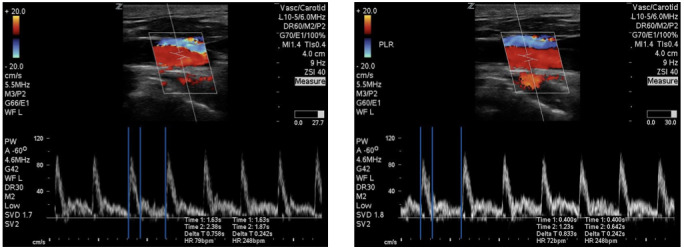

目标:很难确定哪些患者的心输出量会因容量管理而增加。我们建议使用颈动脉血流时间,这是确定患者是否对容量有反应的一种非侵入性方法。方法我们选取了入住重症监护病房并安装了肺动脉导管的患者。我们对被动抬腿前后的心输出量进行颈动脉流速时间和肺动脉导管测量,并将两者进行比较。被动抬腿前与被动抬腿后的测量值若增加 10%,则表明患者对容量有反应。结果:通过金标准肺动脉导管的测定,我们确定了 8 名患者有容量反应。敏感性为 87.5%,特异性为 90.9%。PA-CO 测量值与 CFT 之间的皮尔逊相关系数为 r=0.8316,表明这两种测量值之间具有很强的相关性。结论在使用肺动脉导管的重症患者样本中,我们发现颈动脉血流校正时间与肺动脉导管的心输出量测量值之间存在很强的相关性。

Objectives: Identifying patients who will have an increase in their cardiac output from volume administration is difficult to identify. We propose the use of carotid flow time, which is a non-invasive means to determine if a patient is volume responsive. Methods: Patients admitted to a critical care unit with a pulmonary artery catheter in place were enrolled. We perform a carotid flow time and pulmonary artery catheter measurement of cardiac output pre and post-passive leg raise and comparing the two. An increase of 10% change in the pre- vs. post-passive leg raise measurement would be indicative of a patient who is volume responsive. Results: We identified 8 patients who were volume responsive as determined by the gold standard pulmonary artery catheter. The sensitivity 87.5% and specificity 90.9%. Pearson correlation coefficient between PA-CO measurements and CFT was r=0.8316, indicative of strong correlation between the two measurements. Conclusion: In our patient sample of critically ill patients with pulmonary artery catheters, we found a strong correlation between corrected carotid flow times and cardiac output measurements from pulmonary artery catheters.